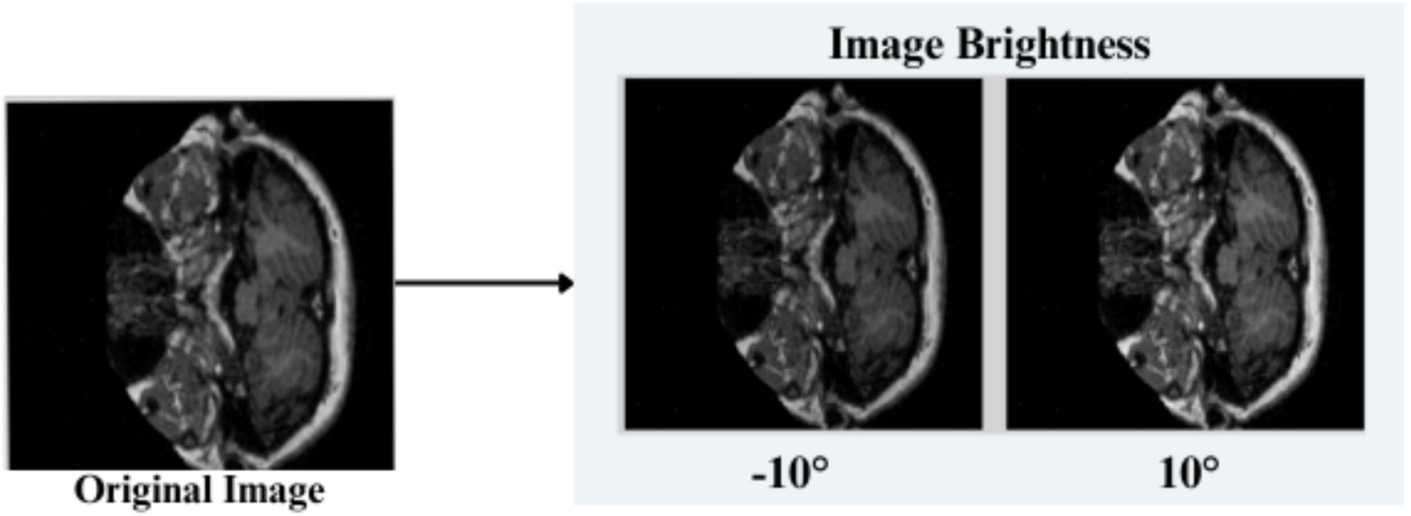

The feature engineering process for this study is to process and augment MRI image data so that relevant patterns associated with Alzheimer’s Disease can be captured. All images are resized to 256 × 256 pixels so that input size is standardized for neural networks, and the same is done to ensure all images have uniform dimensions in order to train the model. It reduces computational complexity, making the processing faster. The next step makes use of image augmentation techniques with the training set, thus artificially increasing the model’s capabilities to generalize new yet unseen data. These techniques include brightness alterations, horizontal and vertical flips, zoom, rotation, and shearing. Horizontal and vertical flipping was performed with 50% chance, and rotation was done clockwise, counter-clockwise, and upside down at random. Cropping was used with a zoom from 0% to a maximum of 4%. Rotation in the −1° to +1° range was used, and shearing transformations were used with ±2° shears in the horizontal and vertical directions. 10% of the images were processed by grayscale conversion and hue adjustment ranging from −15° to +15°, saturation from −25 to +25%, and brightness ranging from −10 to +10%. Those transformations are able to replicate somewhat real-world variations or imperfections that might take place in MRI scans, like different patient positions, variations in lighting, and some variations in the quality of the scan. These techniques help it learn to recognize the patterns related to disease under different conditions and be more robust to variations in the data. Figures 3–9 visually depict the feature engineering operations utilized in this study.

3.3.7 Image brightness

The brightness of the input images is readjusted in the range [0.90, 1.10] as explained in Equation 8